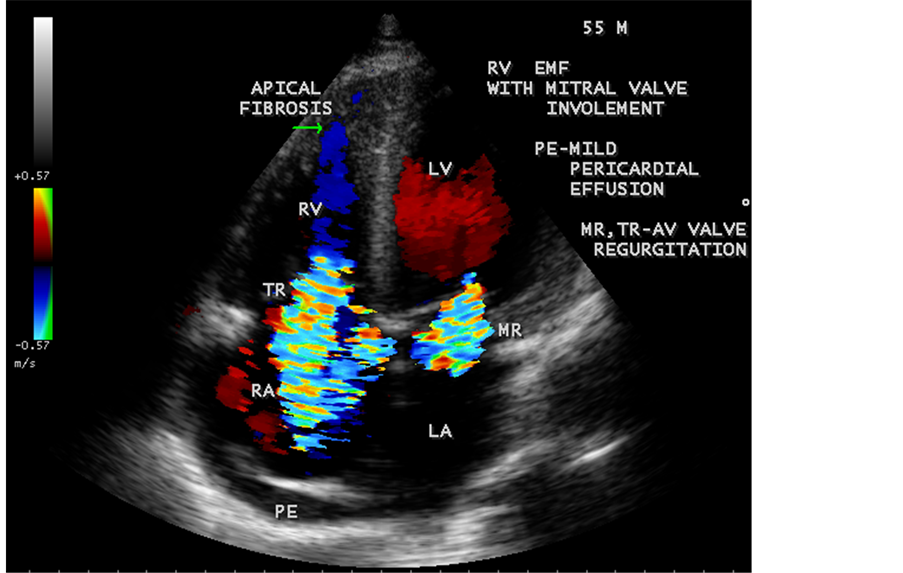

Figure 60. RV EMF with mild pericardial effusion and mitral valve involvement in a 55-year-old male with AV (atrioventricular) valve regurgitation. TR-tricuspid regurgitation, MR-mitral regurgitation.